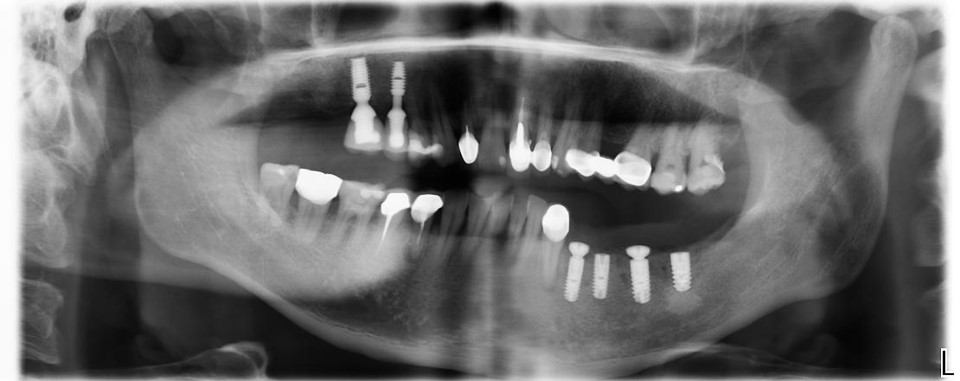

後牙單顆植牙-牙周病-#33-#37

▲(治療前,左下骨高度足夠)

▲用X光看反而缺牙缺的更嚴重,看來我家人平常的口腔護理習慣的真的很差

▼植體植入後還要用X光確認,讓患者可以放心植牙有到位。

▼沒想到用X光看起來也挺牢靠的~~

植體植入後X光確認:#34-37

治療後X光:#33-37